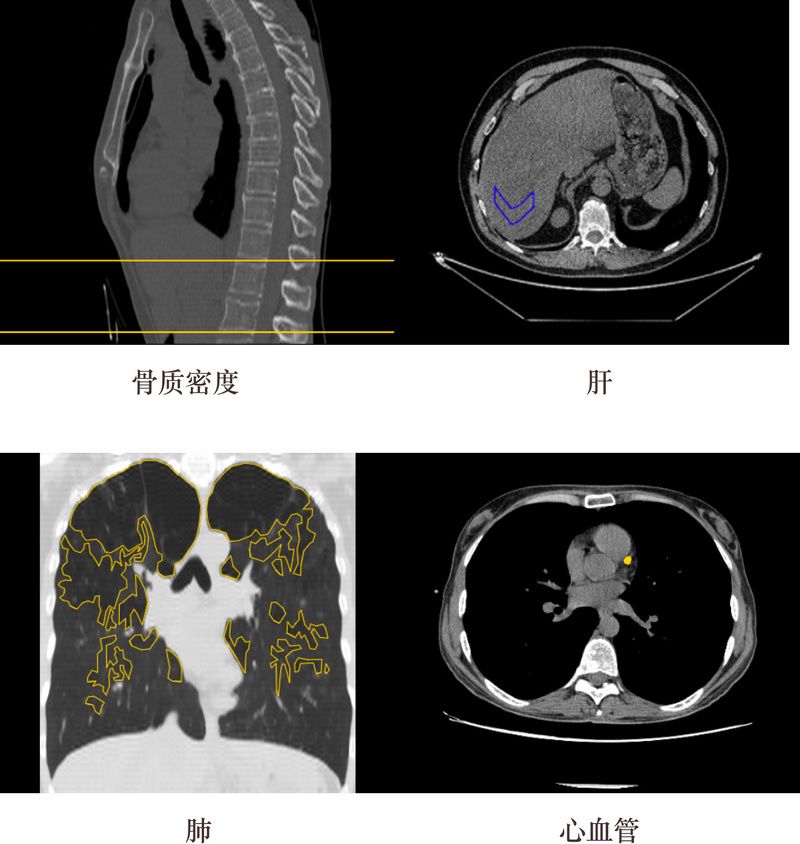

ZEBRA MEDICAL VISION-AI 放射医疗助手

地点:以色列谢法伊姆

Zebra Medical Vision为放射科医师提供了一个支持AI的助手,其可以接收成像扫描并自动分析它们所研究的各种临床发现。研究结果会传递给放射科医师,以帮助医生做出诊断。链接